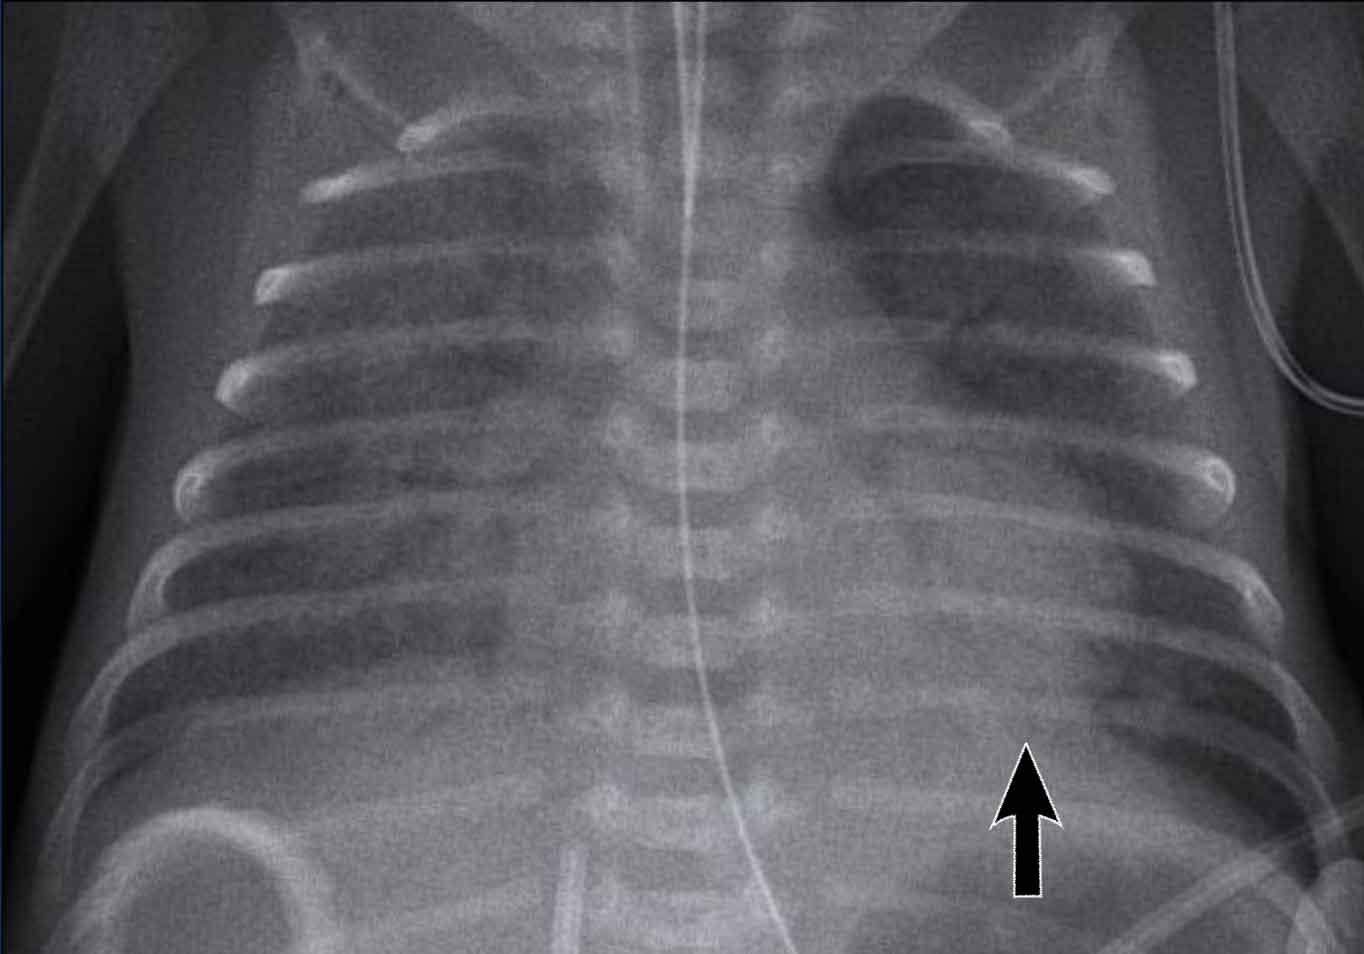

One week old neonate, born at 27 weeks of gestational age.

Image

- Vị trí ống nội khí quản quá sâu, cần được điều chỉnh lại về giữa khí quản.

- Diffuse granular opacification of both lungs.

- Air bronchograms.

- Các mạch máu phổi không còn nhận ra được nữa, nhưng bóng tim vẫn còn có thể nhận ra được.

- Opacification of the left lower lobe caused by atelectasis.

Không phân loại vì trẻ sơ sinh này đang được thở máy.